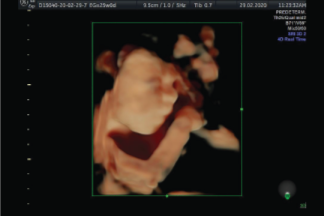

El objetivo principal de esta ecografía es detectar defectos severos en el feto, el flujo en las arterias uterinas y determinar con precisión el tiempo de gestación.

Se evalúa el crecimiento fetal. Se determina la presencia o no de marcadores ecografícos de segundo trimestre para enfermedades cromosómicas (como el Síndrome Down) para el cálculo de riesgo.

Se realiza evaluación estructural fetal de las siguientes estructuras:

• Cabeza: La integridad de los huesos y estructuras cerebrales así como pliegue nucal como marcador para cálculo de riesgo de enfermedades cromosómicas.

• Cara: Perfil fetal, Integridad de huesos, puente nasal, ojos así como integridad de labio y paladar.

• Columna: Evaluación de curvaturas normales en todos sus segmentos, cuerpos vertebrales, canal medular y movilidad normales, así como la integridad de piel. Tórax: estructura cardiaca en su totalidad así como la Frecuencia cardiaca fetal, pulmones fetales y costillas.

• Abdomen: Presencia de estomago, riñones, glándulas suprarrenales normales, diafragma, entrada de cordón umbilical al abdomen y determinación de número de vasos del cordón, integridad de pared abdominal y tamaño vesical.

• Genitales: Determinación de sexo fetal con certeza.

• Extremidades: Presencia de todos los huesos, determinar la movilidad en todos sus segmentos, cuenta de dedos completa.

• Placenta: Determinar su madurez y localización.

• Líquido amniótico: Determinar su cantidad y características.